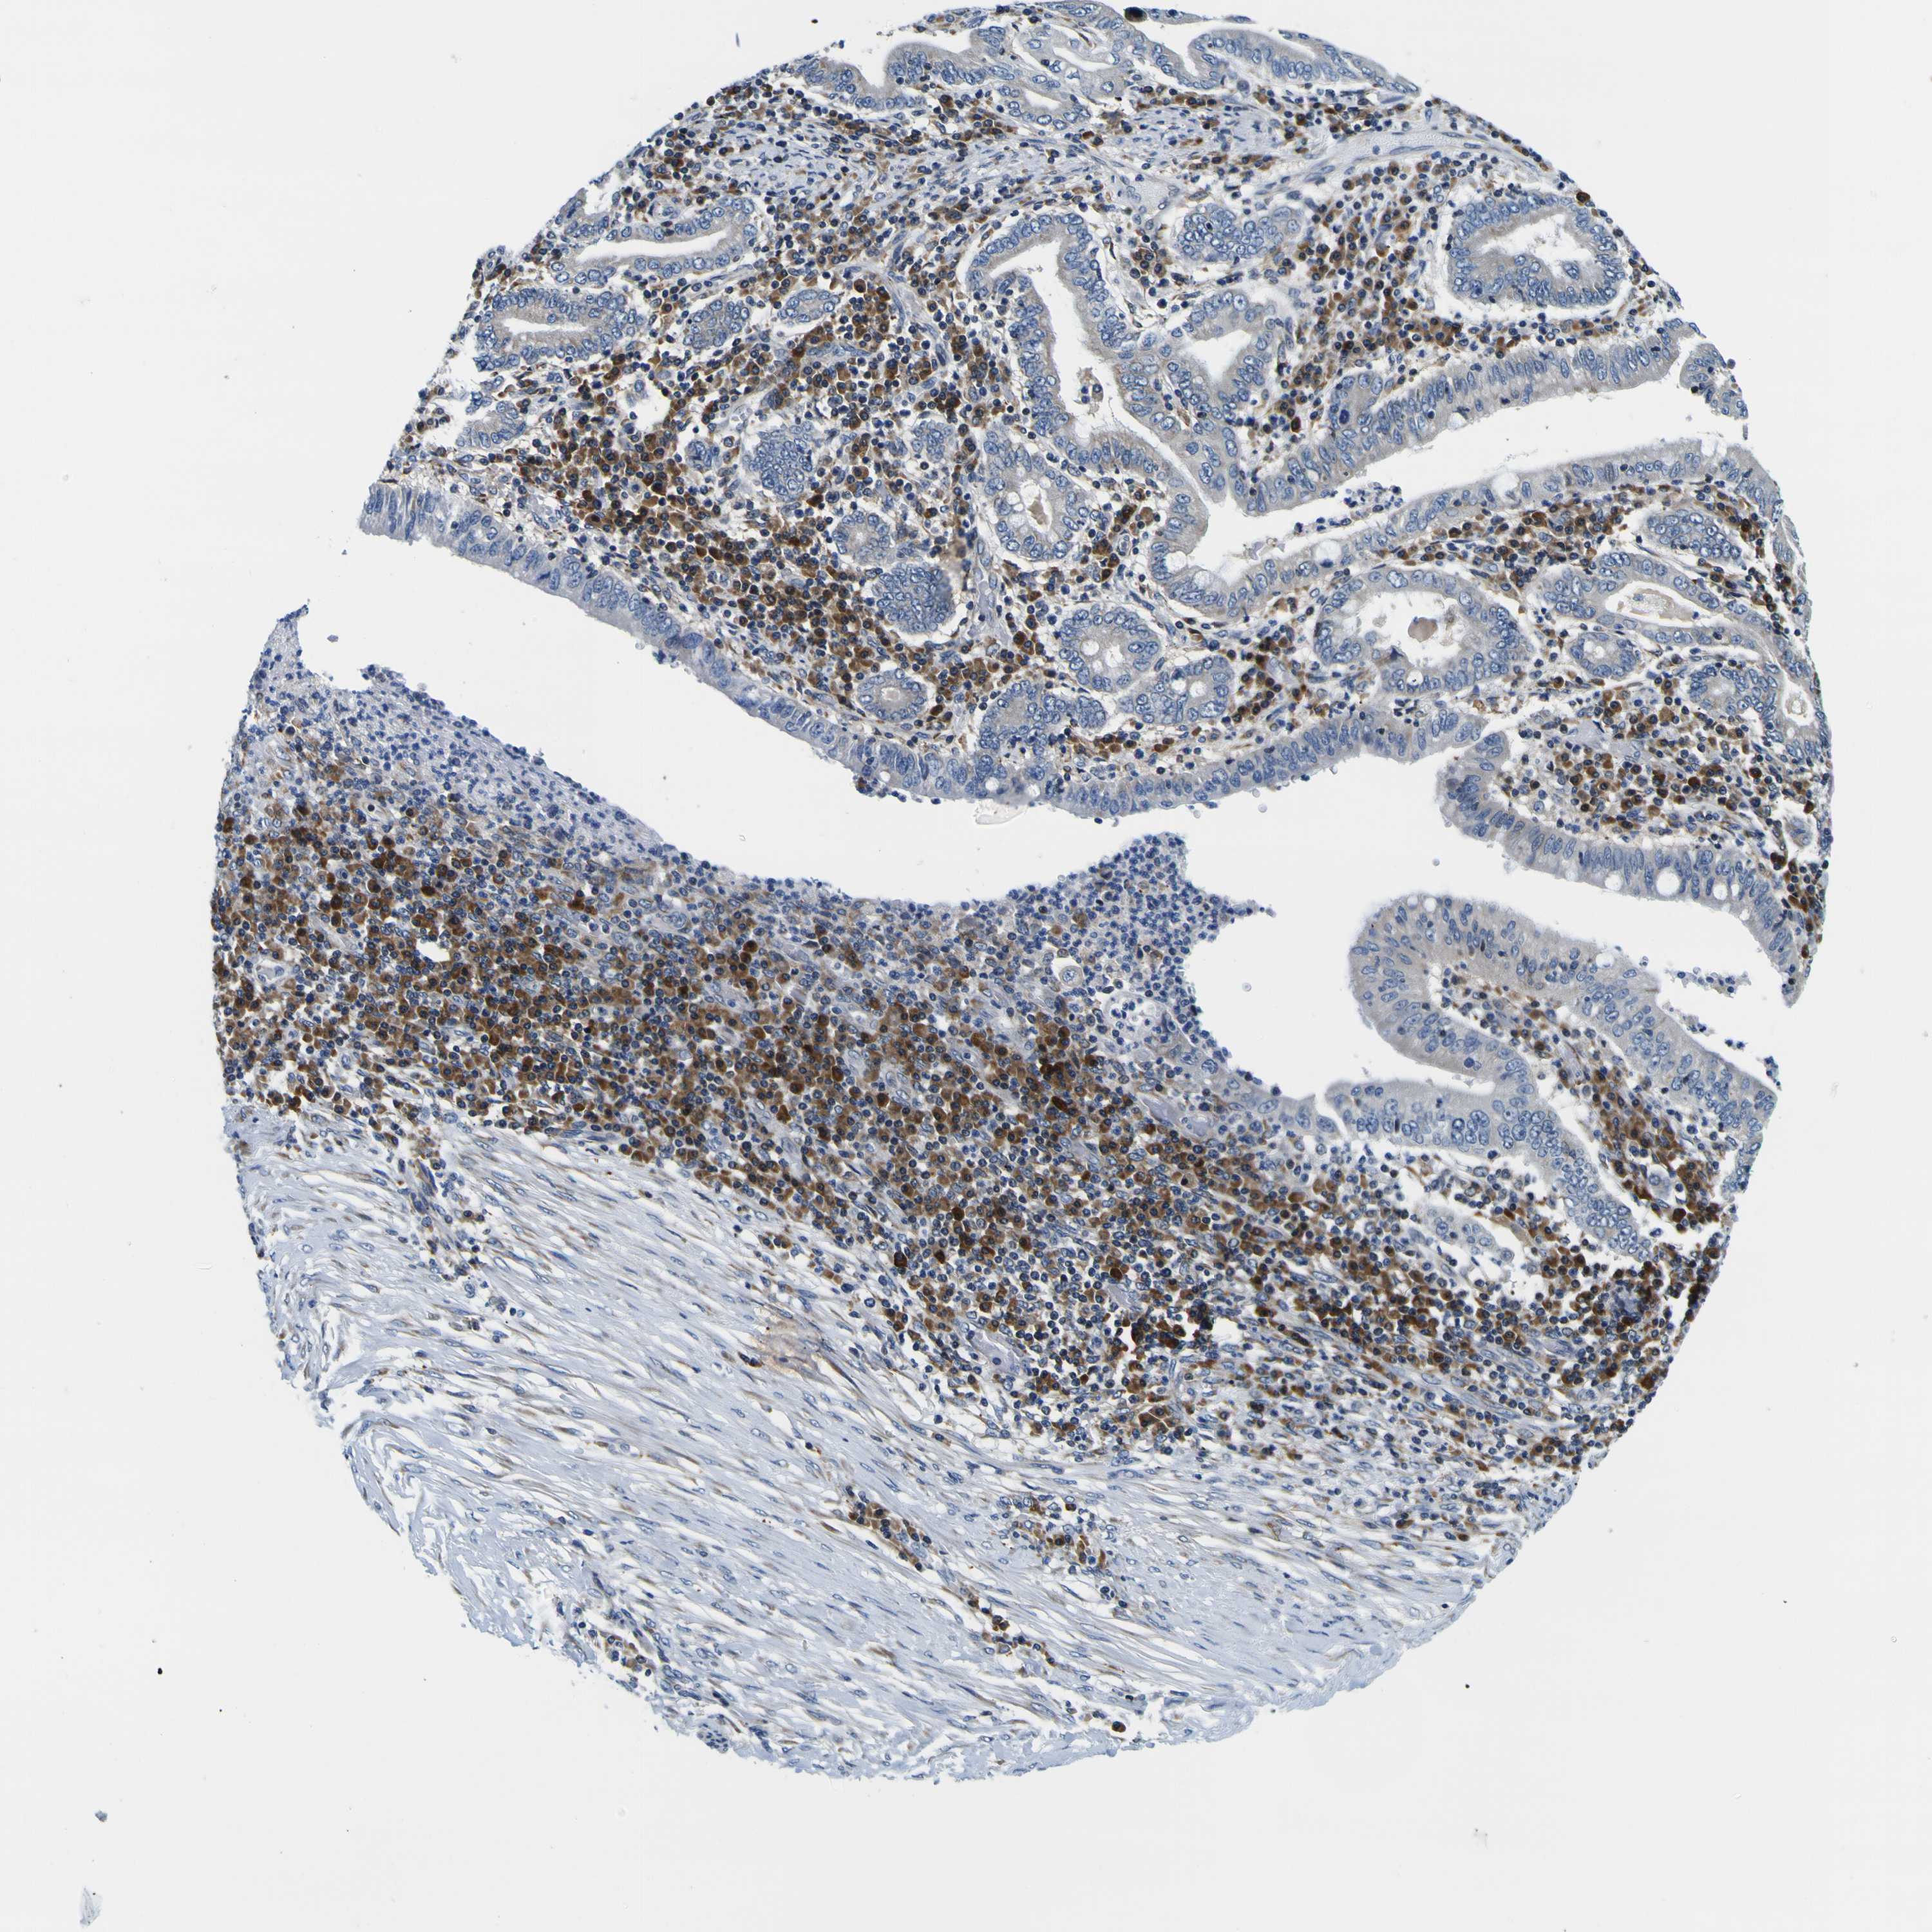

STOMACH CANCER - Protein expressioni

A mouse-over function shows sample information and annotation data. Click on an image to view it in a full screen mode. Samples can be filtered based on level of antibody staining by selecting one or several of the following categories: high, medium, low and not detected. The assay and annotation is described here.

Antibody stainingi

Antibody staining in the annotated cell types in the current human tissue is reported as not detected, low, medium, or high, based on conventional immunohistochemistry profiling in selected tissues. This score is based on the combination of the staining intensity and fraction of stained cells.

Each image is clickable and will lead to virtual microscopy that enables deeper exploration of all samples and also displays staining intensity scores, fraction scores and subcellular localization as well as patient and tissue information for each sample.

Antibody HPA012878

Staining

High

Medium

Low

Not detected

Intensity

Strong

Moderate

Weak

Negative

Quantity

>75%

75%-25%

<25%

None

Location

Nuclear

Cytoplasmic/membranous

Cytoplasmic/membranous,nuclear

Adenocarcinoma, NOS

Adenocarcinoma, High grade